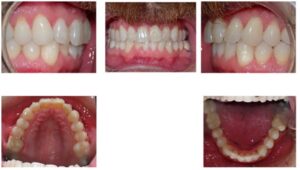

Case 3 – Attachments on UL1, U2s, L2s and L3s

| Initial | 6-month progress, 22 aligners |